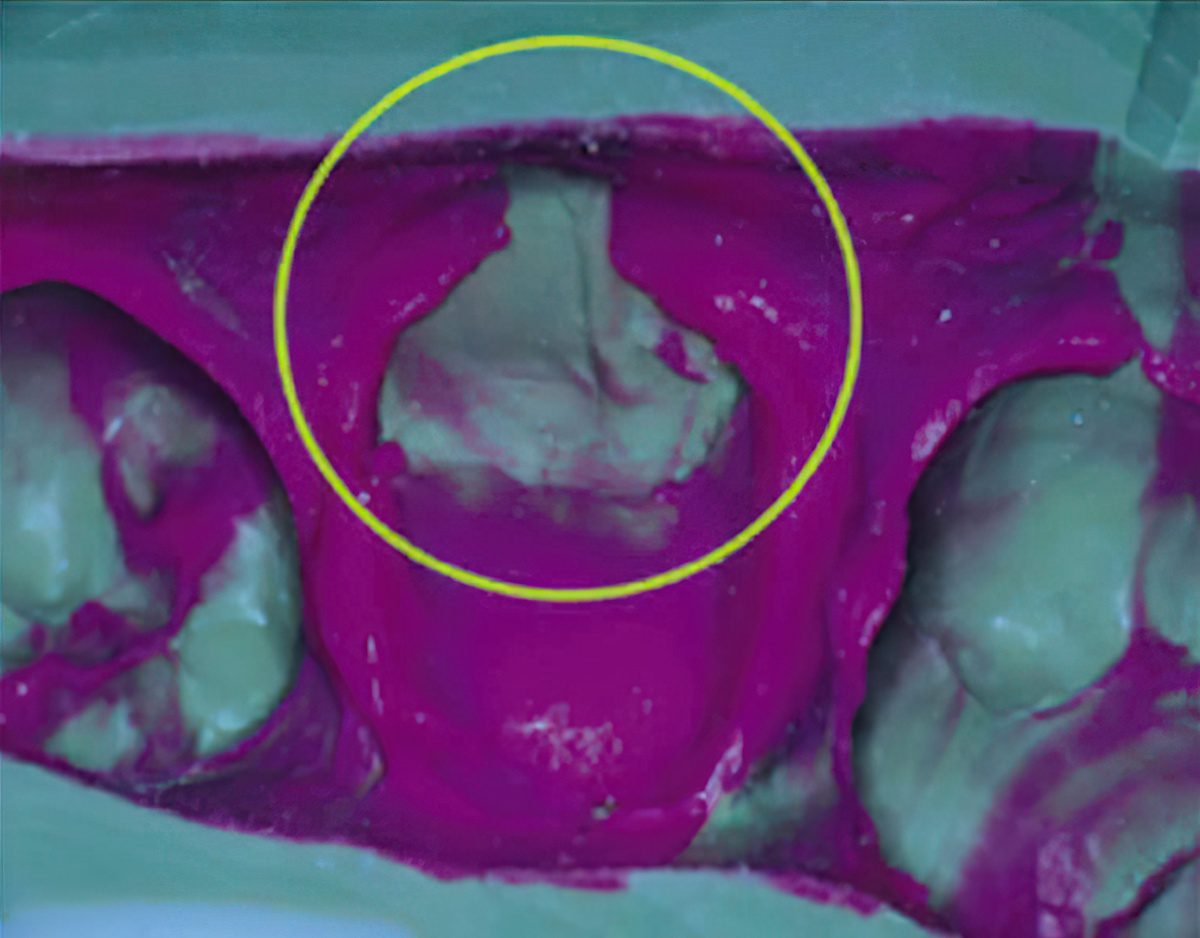

To fabricate a dental cast, dental impression materials are used to copy teeth and surrounding oral structures (see above image). It is vital to the success of a case that the dental impression provides an exact replica of the patient’s oral structures in order to ensure a precise fitting restoration.

2. Voids, especially those found on the margins, can cause restorations that are short and/or open. These can occur for a variety of reasons, including defective material, bubbles in the syringe, and blood/saliva in the area. (Figure 2, shown below in purple)

4. Unable to read the margins. This is one of the most common issues that dental labs experience with traditional impression methods. This can lead to a restoration that does not fit. Again this can be caused by blood and saliva, poor retraction, and poor impression material. (Figure 3 shown below in yellow)